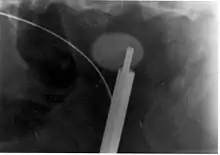

A lithotriptor machine with a mobile fluoroscopic system ("C-arm") is seen in an operating room; other equipment is seen in the background including an anesthesia machine.

Extracorporeal shock wave lithotripsy (ESWL) is a noninvasive technique for the removal of kidney stones. Most ESWL is carried out when the stone is present near the renal pelvis. ESWL involves the use of a lithotriptor machine to deliver externally applied, focused, high-intensity pulses of ultrasonic energy to cause fragmentation of a stone over a period of around 30–60 minutes. Following its introduction in the United States in February 1984, ESWL was rapidly and widely accepted as a treatment alternative for renal and ureteral stones.[95] It is currently used in the treatment of uncomplicated stones located in the kidney and upper ureter, provided the aggregate stone burden (stone size and number) is less than 20 mm (0.8 in) and the anatomy of the involved kidney is normal.[96][97]

For a stone greater than 10 millimetres (0.39 in), ESWL may not help break the stone in one treatment; instead, two or three treatments may be needed. Some 80-85% of simple renal calculi can be effectively treated with ESWL.[7] A number of factors can influence its efficacy, including chemical composition of the stone, presence of anomalous renal anatomy and the specific location of the stone within the kidney, presence of hydronephrosis, body mass index, and distance of the stone from the surface of the skin.[95] Common adverse effects of ESWL include acute trauma, such as bruising at the site of shock administration, and damage to blood vessels of the kidney.[98][99] In fact, the vast majority of people who are treated with a typical dose of shock waves using currently accepted treatment settings are likely to experience some degree of acute kidney injury.[95]